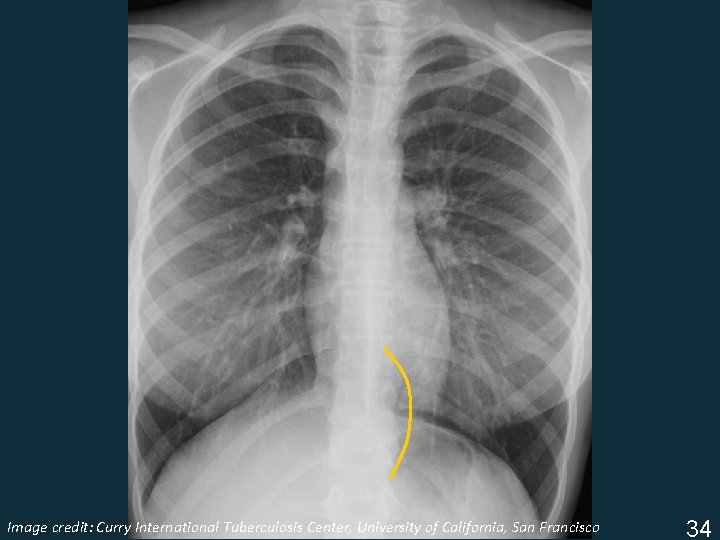

Image Tuberculosis Center, University of California, San Francisco ISTC TBcredit: Training Curry Modules. International 2009 34

Lymphadenopathy § Infrahilar window (right hilar and/or subcarinal) § Left hilar § Subcarinal Image Tuberculosis Center, University of California, San Francisco ISTC TBcredit: Training Curry Modules. International 2009 35

Lymphadenopathy § Infrahilar window (right hilar and/or subcarinal) Image Tuberculosis Center, University of California, San Francisco ISTC TBcredit: Training Curry Modules. International 2009 35

Lymphadenopathy § Left hilar Image Tuberculosis Center, University of California, San Francisco ISTC TBcredit: Training Curry Modules. International 2009 35

Lymphadenopathy § Subcarinal Image Tuberculosis Center, University of California, San Francisco ISTC TBcredit: Training Curry Modules. International 2009 35